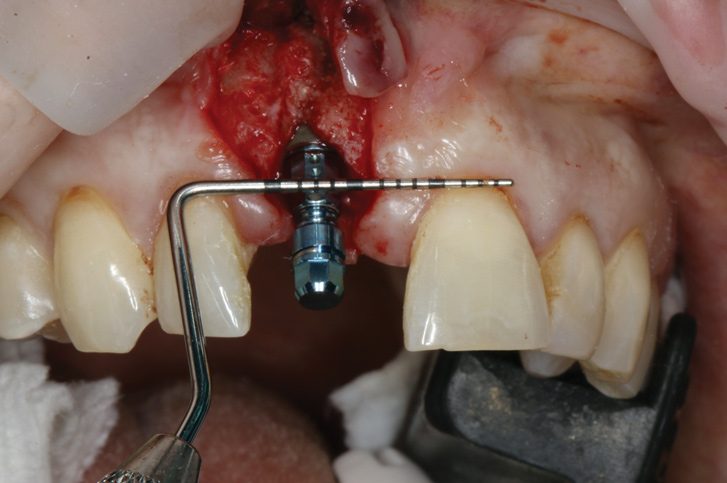

(16.) Full-thickness flap elevation to expose the tenting screw and gain access for anticipated additional bone grafting following implant placement.

Figure 16

(17.) Implant placed 1-mm distal to the midline of the edentulous space, corresponding with the planned location of the gingival zenith. Note the lack of sufficient bone buccal to the implant that necessitated further grafting.

Figure 17

Prior to the initiation of the surgery, the surgical guide was tried in to confirm proper seating and stability (Figure 15). A flapless approach was not considered because the need for further bone grafting at the time of implant placement had been anticipated through the digital planning. A slightly palatal crestal incision was made, followed by two vertical incisions on the mesial and distal aspects of the edentulous site in order to preserve the papilla and avoid additional esthetic compromise to the anterior sextant. Next, a full-thickness flap was elevated to facilitate removal of the tenting screw and permit visualization of the buccal plate (Figure 16). A standard guided protocol was followed to place the implant, and its final position mirrored that of the digital plan. As predicted, the prosthetically driven implant position resulted in an insufficient buccal plate (Figure 17); therefore, additional guided bone regeneration was performed to reinforce the area and prevent future breakdown (Figure 18 and Figure 19). Making periosteal incisions could have compromised the blood supply to the flap, so instead, it was stretched in order to achieve tension free coronal advancement.31The flap was secured utilizing horizontal mattress sutures with additional supportive interrupted sutures to ensure primary closure (Figure 20). An immediate postoperative periapical radiograph (Figure 21) and CBCT scan (Figure 22) were taken, demonstrating a final implant position centered with the planned location of the gingival zenith.